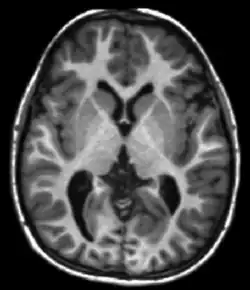

The central objects are shapes or forms in computational anatomy, one set of examples being the 0,1,2,3-dimensional submanifolds of , a second set of examples being images generated via medical imaging such as via magnetic resonance imaging (MRI) and functional magnetic resonance imaging.

The landmarks are a collections of points with no other structure, delineating important fiducials within human shape and form (see associated landmarked image). The sub-manifold shapes such as surfaces are collections of points modeled as parametrized by a local chart or immersion , (see Figure showing shapes as mesh surfaces). The images such as MR images or DTI images , and are dense functions are scalars, vectors, and matrices (see Figure showing scalar image).